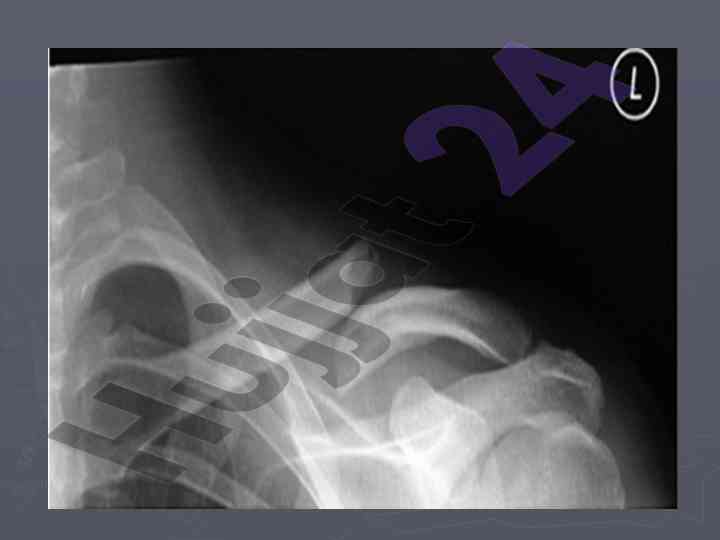

Elka kamari va yelka suyaklarining sinishlari haqida tahlil, belgilari va davolash usullari. Bolalarda kam uchraydigan kurak sinishlari, tashxis va davo usullari.